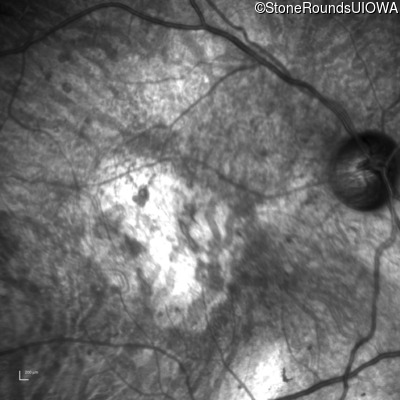

Infrared Fundus Photograph - Right - Hand Motion sc

Exemplar

Infrared Fundus Photograph - Left - Hand Motion sc